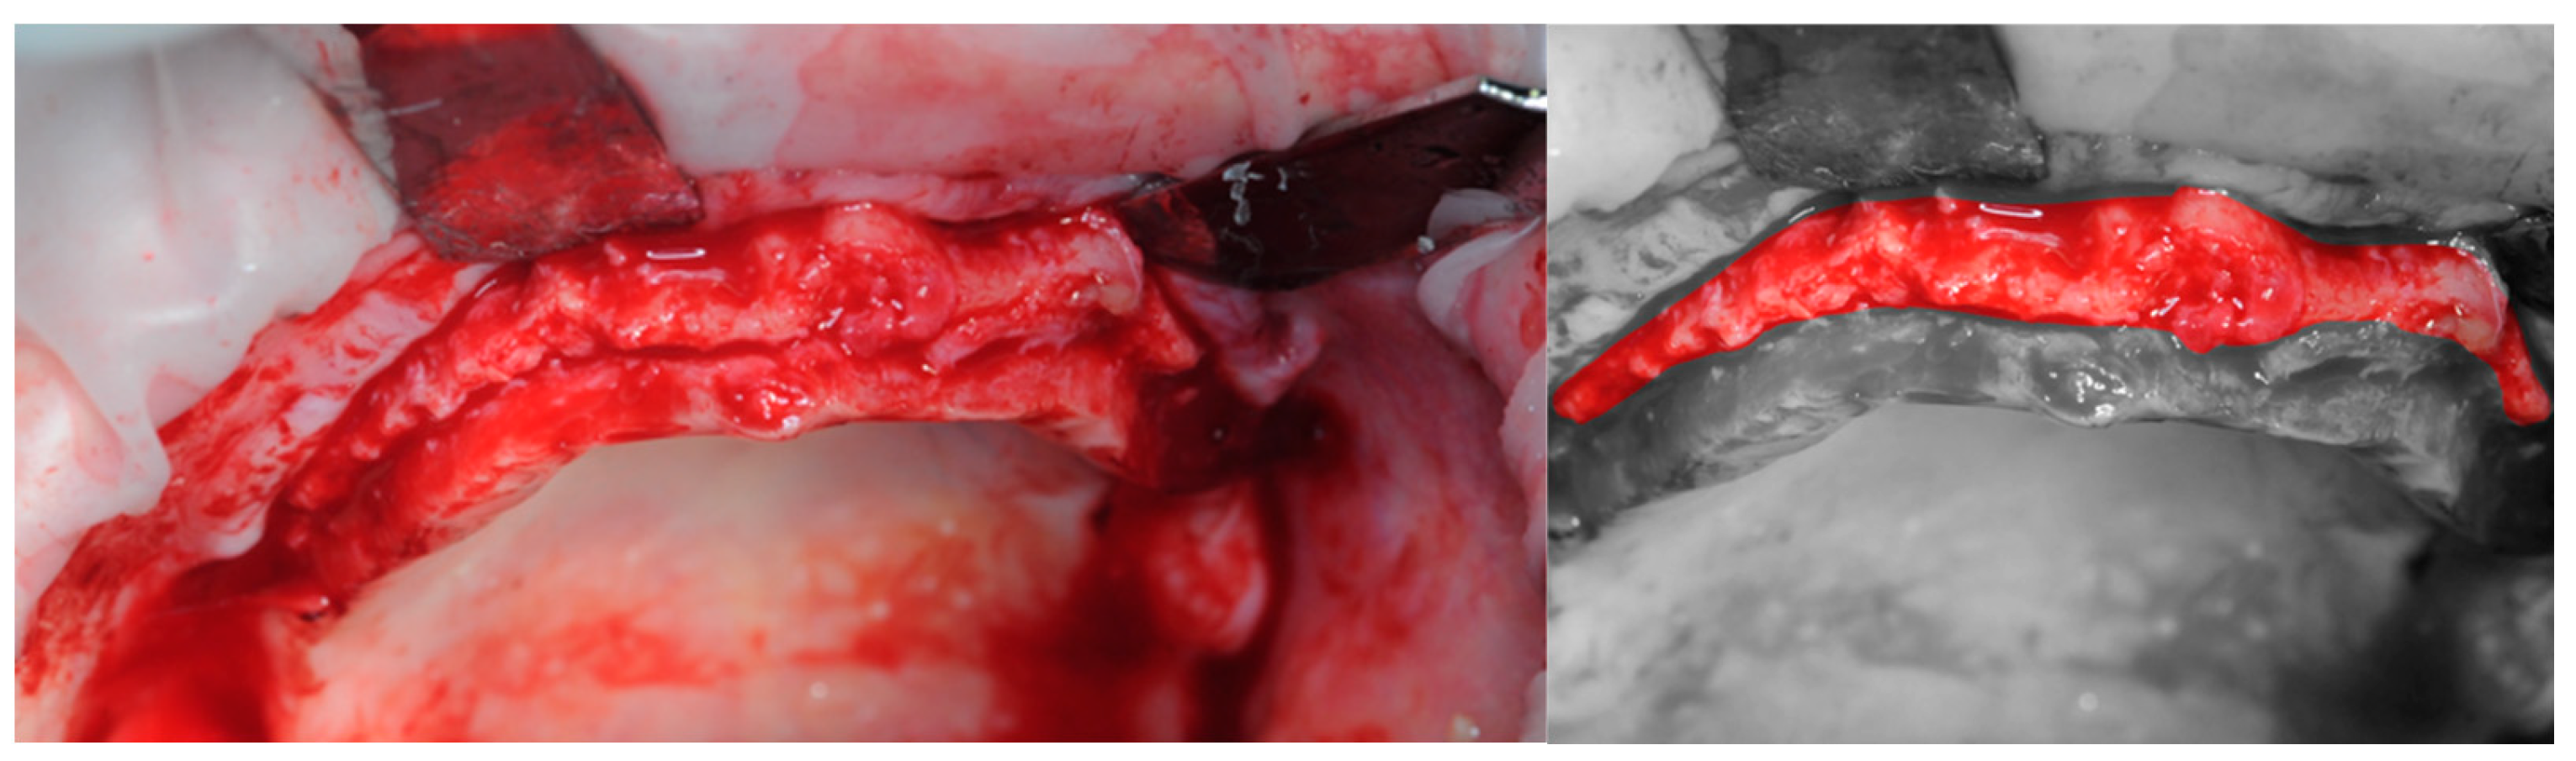

2.3. Re-Entry Surgery

3.3. Hard Tissues Gain